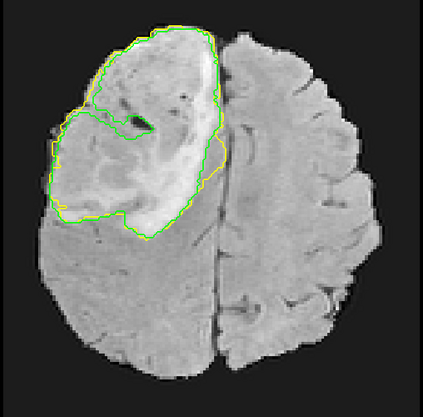

Despite the state-of-the-art performance for medical image segmentation, deep convolutional neural networks (CNNs) have rarely provided uncertainty estimations regarding their segmentation outputs, e.g., model (epistemic) and image-based (aleatoric) uncertainties. In this work, we analyze these different types of uncertainties for CNN-based 2D and 3D medical image segmentation tasks. We additionally propose a test-time augmentation-based aleatoric uncertainty to analyze the effect of different transformations of the input image on the segmentation output. Test-time augmentation has been previously used to improve segmentation accuracy, yet not been formulated in a consistent mathematical framework. Hence, we also propose a theoretical formulation of test-time augmentation, where a distribution of the prediction is estimated by Monte Carlo simulation with prior distributions of parameters in an image acquisition model that involves image transformations and noise. We compare and combine our proposed aleatoric uncertainty with model uncertainty. Experiments with segmentation of fetal brains and brain tumors from 2D and 3D Magnetic Resonance Images (MRI) showed that 1) the test-time augmentation-based aleatoric uncertainty provides a better uncertainty estimation than calculating the test-time dropout-based model uncertainty alone and helps to reduce overconfident incorrect predictions, and 2) our test-time augmentation outperforms a single-prediction baseline and dropout-based multiple predictions.